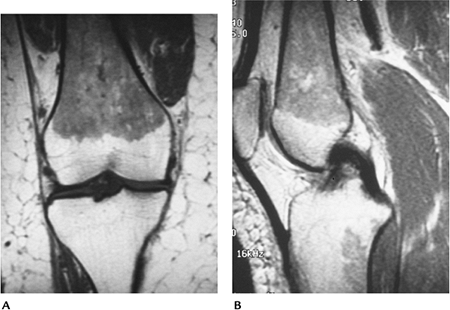

FIGURE 12-2 Marrow hyperplasia in a long-distance runner. Coronal (A) and sagittal (B)

T1-weighted images showing low intensity marrow in the femoral diaphysis and metaphysis with a focal area of hyperplasia in the tibia. Cortical bone is normal, and there are no soft tissue abnormalities. |